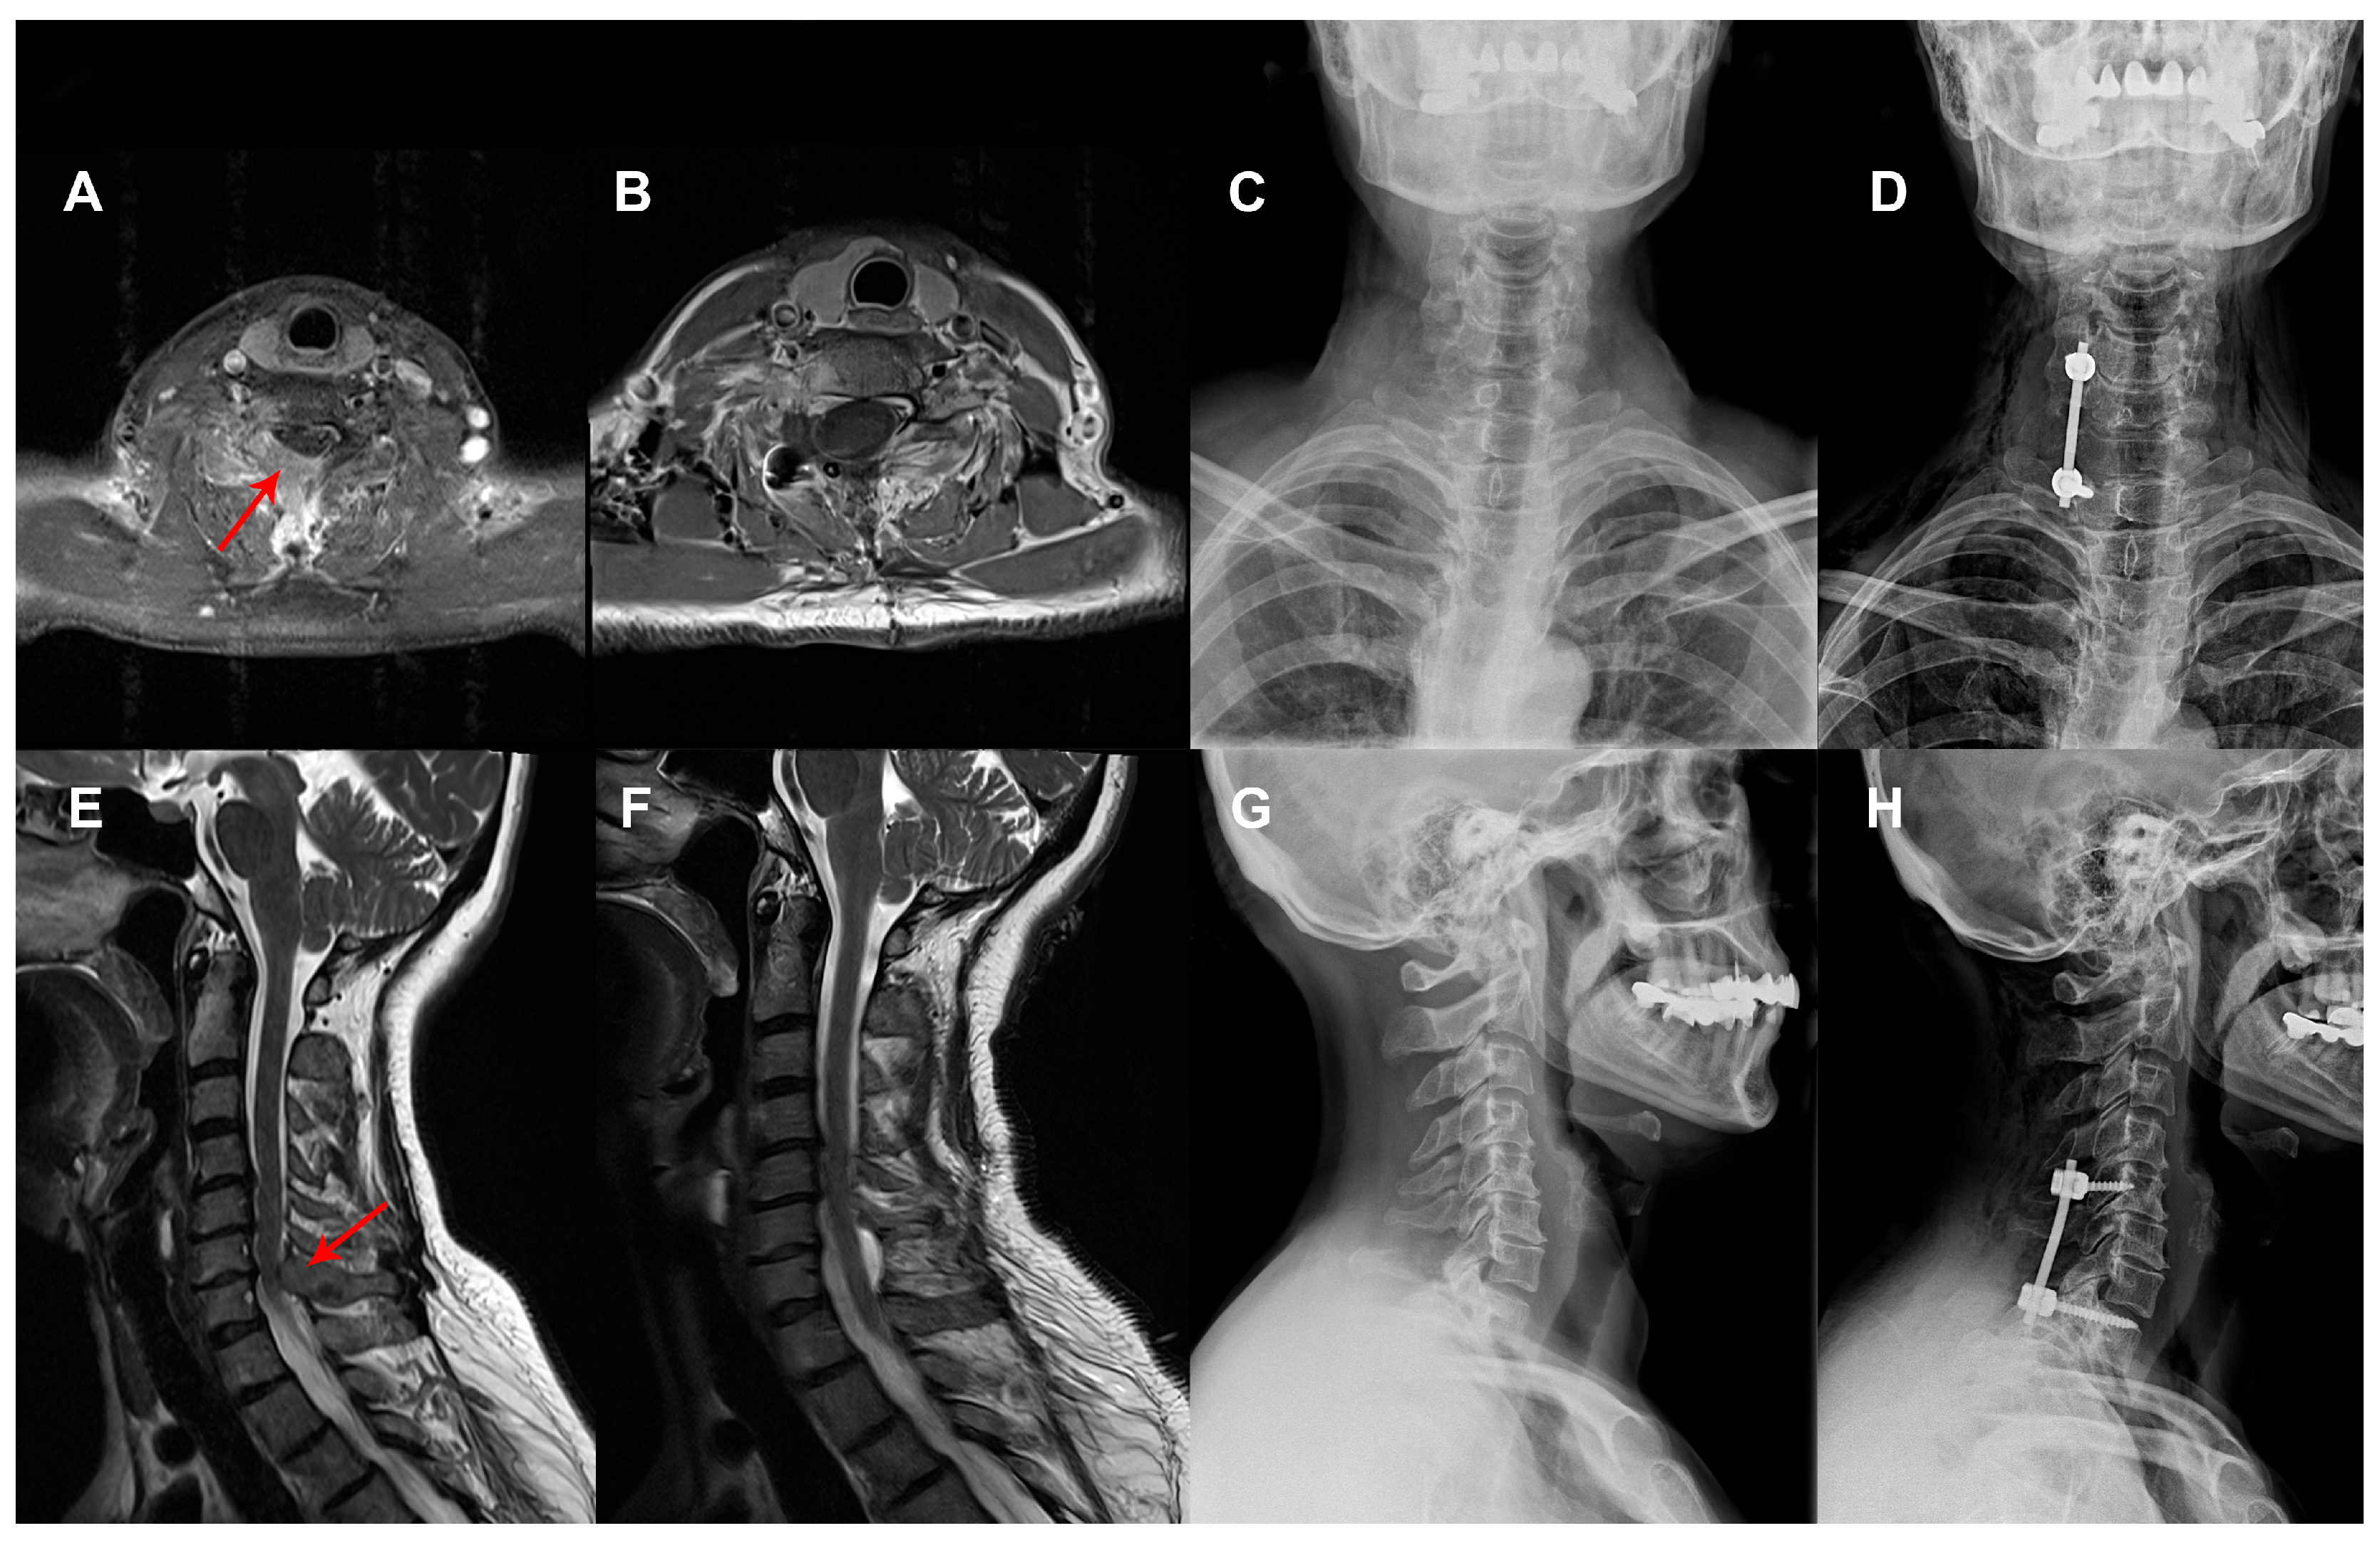

2.3. Surgical Technique